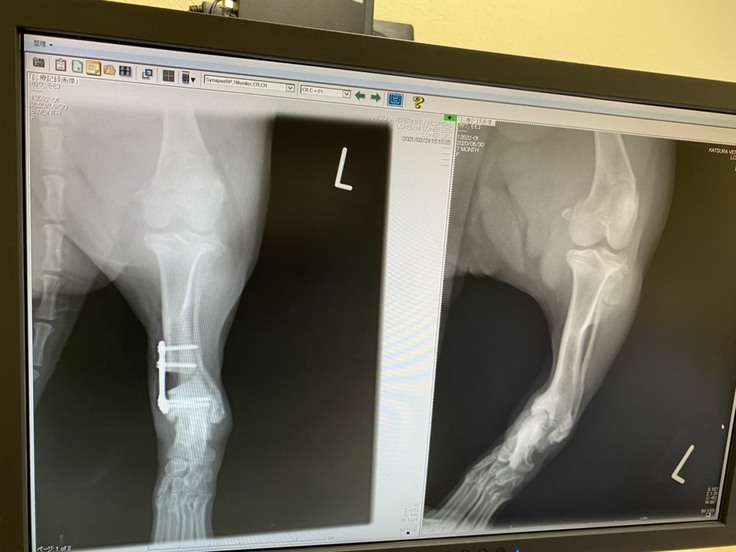

カツラ犬猫病院 整形外科

▼1回目の手術が終了しました

令和3年3月24日(水曜日)

予定通り最初の手術が終了しました。

手術は無事成功です。

先生も理想的な角度で固定ができましたと!

ただ固定するピンが関節の5㎜上で固定をしているため

個人的に少し心配ですが、大きな問題ではないようです。

足は以前に比べると明らかに真っすぐになりました。